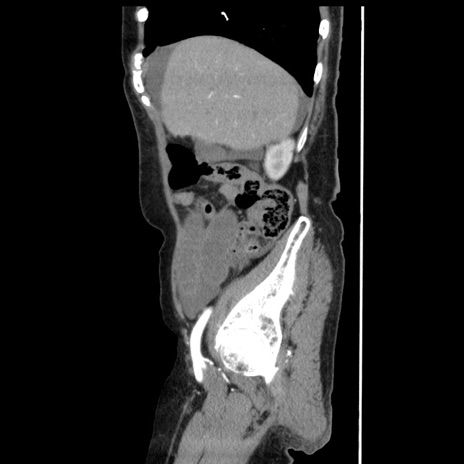

症例1(矢状断像)

【症例】80歳代女性

【主訴】腹痛

【現病歴】8時間前から腹痛あり来院。

【既往歴】糖尿病、脂質異常症、子宮体癌にて子宮全摘術

【身体所見】意識清明・会話良好だが腹痛で苦悶様、全腹部にわたって反跳痛と圧痛あり

【データ】WBC 13600、CRP 0.14、LDH 224、CK 90